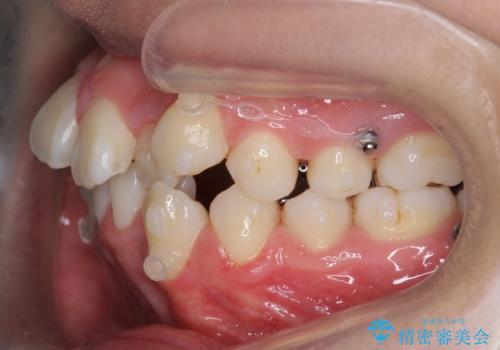

八重歯 抜かずにマウスピース矯正治療

- 八重歯を主訴に来院。

(2)奥歯を後ろに下げ、歯並びを拡大し、歯を少し削って抜かずにインビザライン矯正 矯正用ミニスクリュー併用 口元は下がらない

リファインメントもなく、1回で治療が終了しました。大変うまくいったケースです。

主治医としては、前歯の並びをもう少しこだわりたかったのですが、満足度が高く、リファインメントは希望されませんでした。

- 95万円(インビザライン:85万円 付加装置:ミニスクリュー10万円)費用は治療当時の料金となります